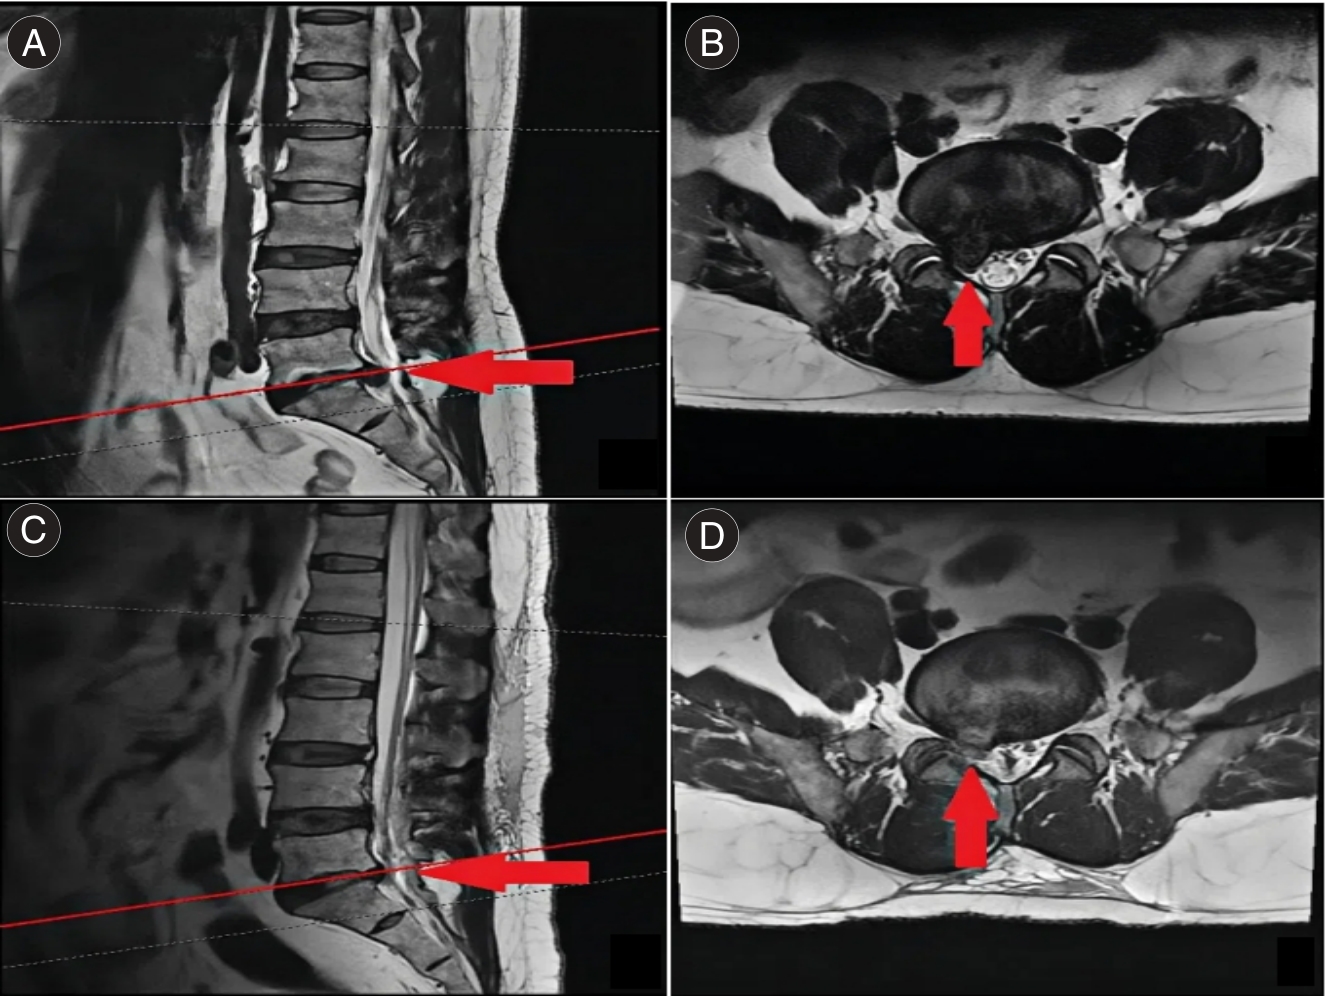

目的 分析经Kambin三角入路与经后方椎板间隙入路脊柱内镜手术对腰椎间盘突出症(LDH)伴侧隐窝狭窄患者的影响。 方法 选取152例LDH伴侧隐窝狭窄患者,按照手术入路方式分为Kambin组(n = 77)与椎板间隙组(n = 75),两组分别经Kambin三角入路、经后方椎板间隙入路。对比两组手术相关指标、视觉模拟评分法(VAS)、Oswestry功能障碍指数(ODI)评分、侧隐窝狭窄面积、并发症发生率。 结果 Kambin组手术时间及术后住院时间均短于椎板间隙组(P < 0.05);Kambin组术后1 d、1个月的VAS评分均低于椎板间隙组(P < 0.05);两组术后1、3个月的ODI评分比较无明显差异(P > 0.05);两组术后侧隐窝狭窄面积比较无明显差异(P > 0.05)。椎板间隙组出现1例术后感染。 结论 Kambin入路手术时间更短,两种入路均有效改善功能、扩大侧隐窝,椎板间隙入路需优化减少并发症。

Objective To evaluate and compare the effects of endoscopic spinal surgery performed via the Kambin's triangle approach and the posterior interlaminar approach on patients diagnosed with lumbar disc herniation (LDH) and concurrent lateral recess stenosis. Methods The clinical data of patients who underwent lumbar pedicle screw fixation at our hospital between January 2017 and December 2023 were retrospectively analyzed. Patient information including sex, age, diagnosis, surgical level, presence and type of postoperative neurological complications was recorded. Based on postoperative CT scans, the zone and grade of screw penetration were assessed, and the distribution of different types of pedicle screw penetration was documented. The association between specific types of pedicle screw penetration and the occurrence of postoperative neurological symptoms was then analyzed. Results The operation time and postoperative hospital stay in the Kambin group were significantly shorter than those in the interlaminar group (P < 0.05). On postoperative day 1 and at 1 month postoperatively, the VAS scores in the Kambin group were significantly lower than those in the interlaminar group (P < 0.05). No significant differences were observed between the two groups in terms of ODI scores on postoperative day 1 and at 3 months postoperatively, or in the postoperative area of lateral recess stenosis (P > 0.05). One case of postoperative infection was reported in the interlaminar group. Conclusions For patients with LDH and lateral recess stenosis, endoscopic spinal surgery via the Kambin's triangle approach is associated with a shorter operative duration. Both the Kambin's triangle approach and the interlaminar approach can effectively improve functional outcomes and decompress the lateral recess. However, the interlaminar approach requires further optimization to minimize the risk of complications.